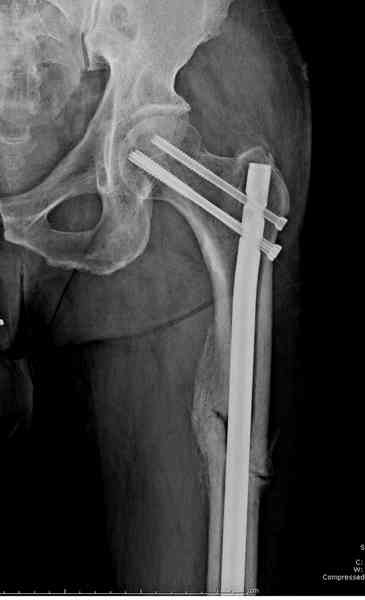

Здесь представлены снимки больного 65 лет, поступившего с диагнозом перелом

бедра после автоаварии.

В первый же день произведено антеградное штифтованием DePuy Trochanteric Nail.

На второй день (7) обнаружен пропущенный перелом,

и проведены шурурпы через и спереди штифта без удаления.

Послеоперационные снимки